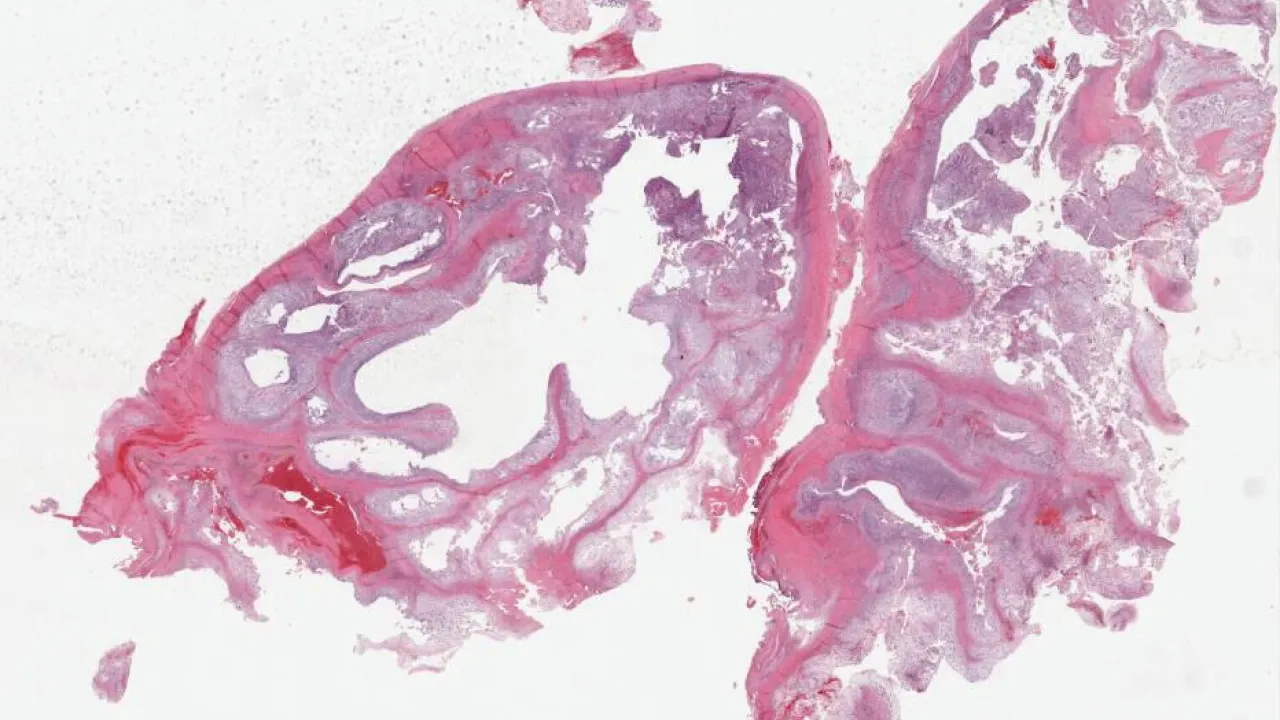

Soft Tissue, Schwannoma

Soft Tissue, Solitary fibrous tumour

Soft Tissue, Glomus tumour

Soft Tissue, Giant cell tumour of tendon sheath

Soft Tissue, Rheumatoid nodules

Soft Tissue, Traumatic neuroma

Soft Tissue, Inclusion body fibromatosis